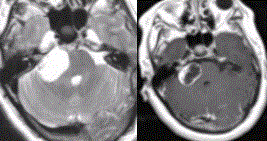

- 多项选择题4.病例诊断为(提示进一步MR检查结果如下图)

A、CPA区脑膜瘤

B、CPA区听神经鞘瘤

C、三叉神经鞘瘤

D、CPA区皮样囊肿

E、CPA区表皮样囊肿

F、CPA区蛛网膜囊肿

G、面神经鞘瘤

关注下方微信公众号,搜题查看答案